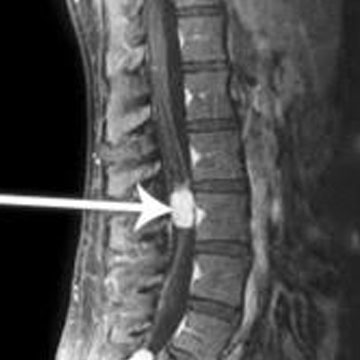

Spinal Tumor